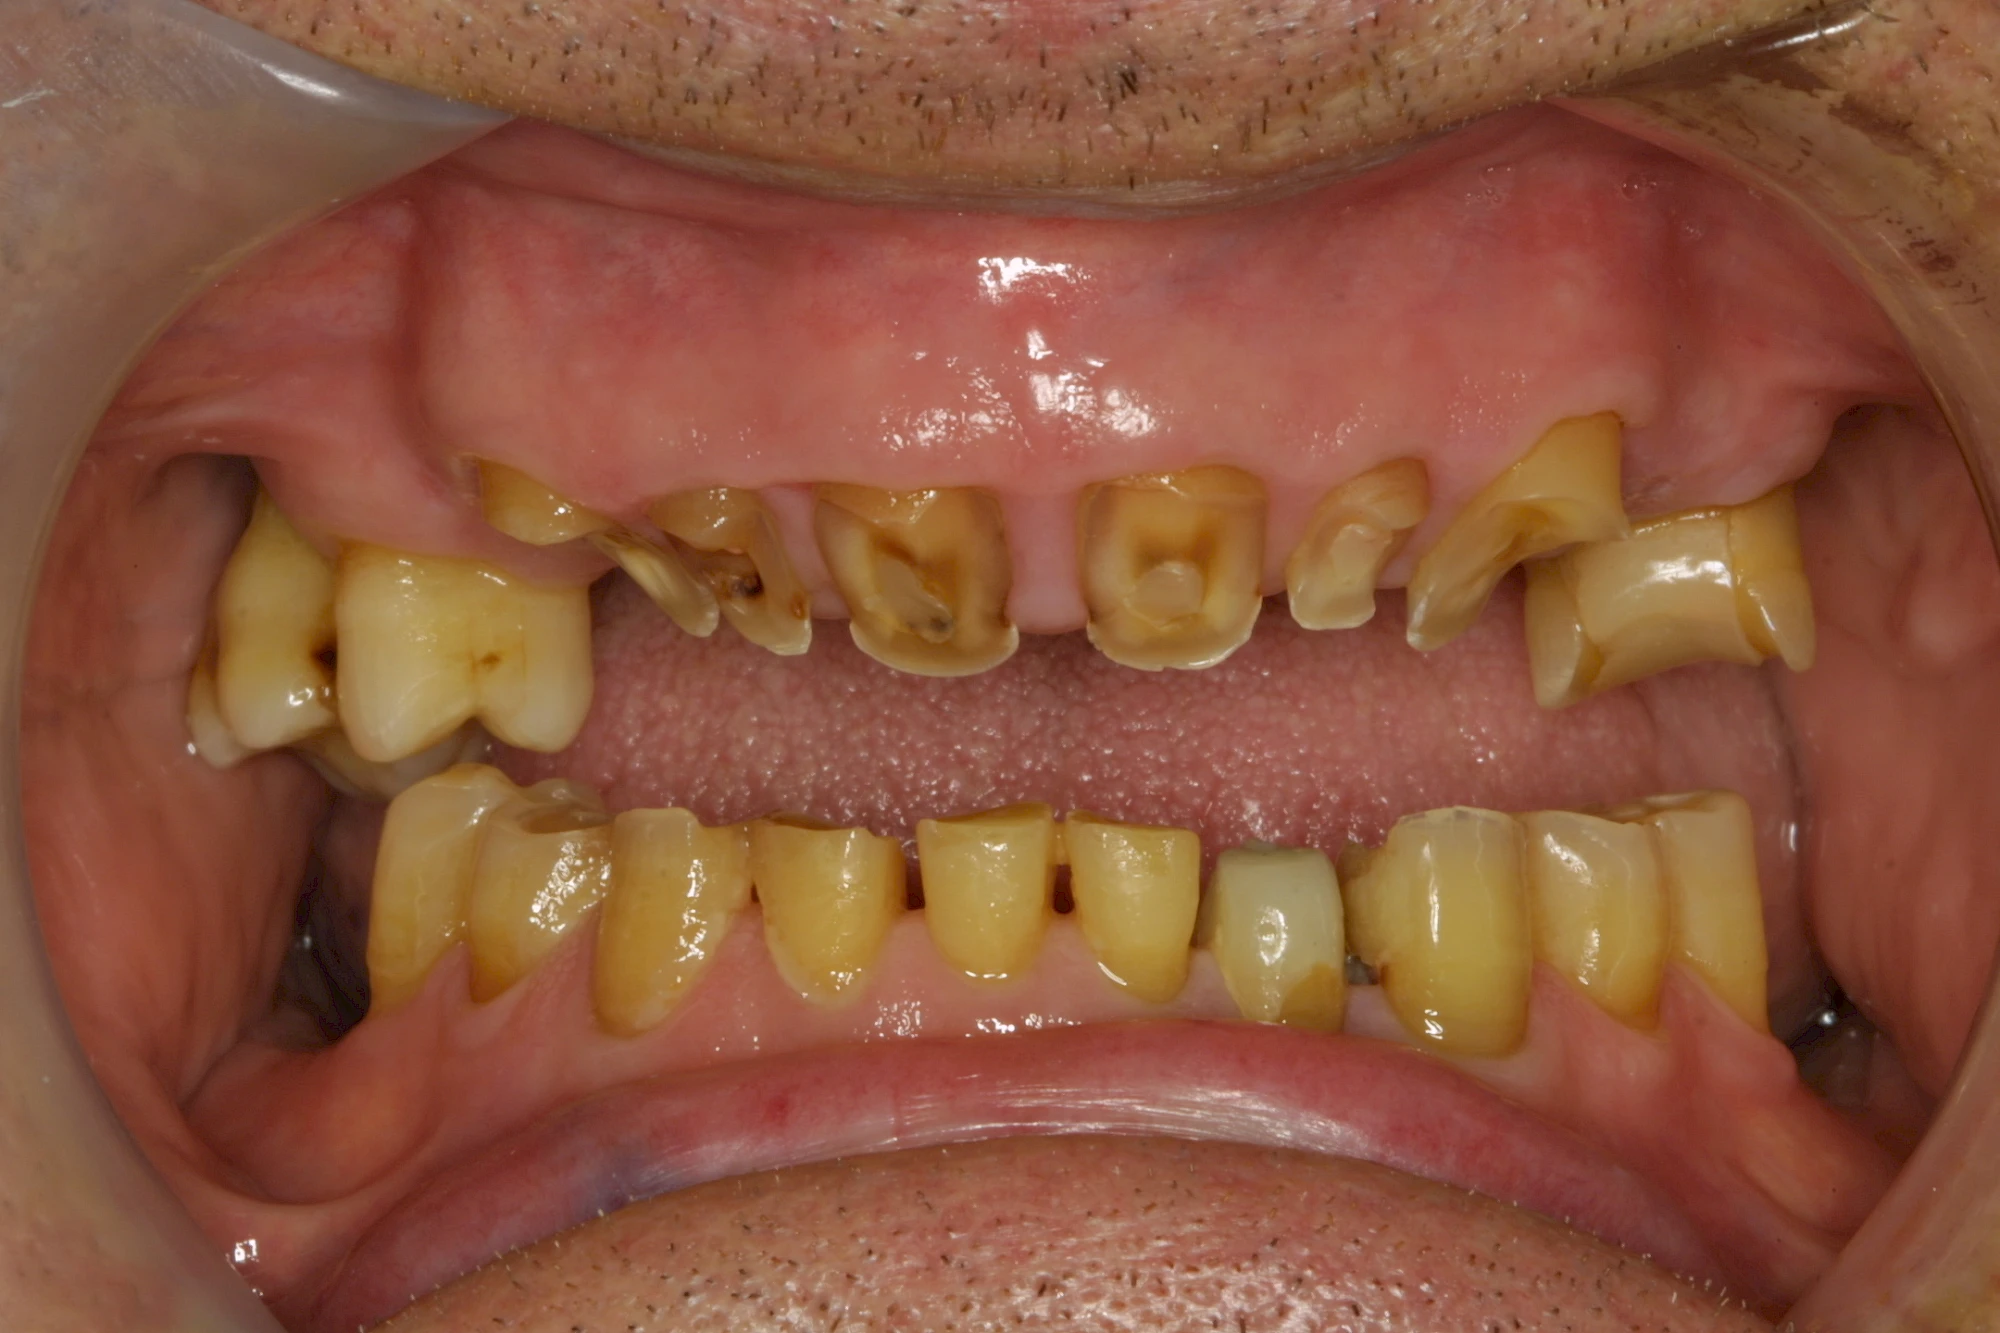

Über die Zeit können verschiedene Prozesse die Zahnhartsubstanzen aufzehren:

- Abnutzung durch Kauen (Abrasion) oder duch durch übermäßiges Knirschen bzw. Pressen (Attrition)

- Säurebedingte Auswaschung (Erosion)

- Knirschen bzw. Pressen und ungünstige Putztechnik (Druck): keilförmige Defekte

Auswaschung (Erosion) dagegen ist eine Verschleißerscheinung der Zähne aufgrund von immer wiederkehrenden Säureangriffen durch die Nahrung, verstärkt zum Beispiel durch den Genuss säurehaltiger Getränke oder Speisen. Auch bei Menschen mit einer Essstörung (z. B. Bulimie) können die Zähne durch die Magensäure ausgewaschen erscheinen.

Eine Sonderform sind sogenannte keilförmige Defekte im Bereich der Zahnhälse. Hier geht man davon aus, dass Knirschen und Pressen in Kombination mit falschen Putzgewohnheiten (zu hoher Putzdruck, Verwendung von Zahnpasta mit hohen Abrasionswerten) eine Rolle spielen.